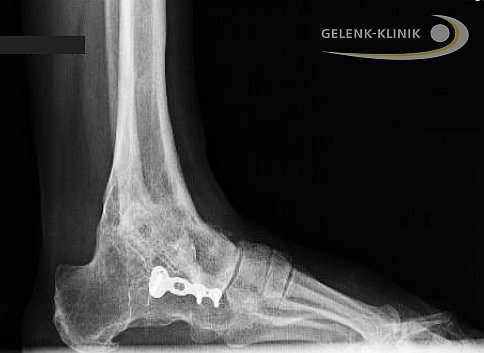

Versteifung des Sprunggelenks nach Revision einer Sprunggelenksprothese. Bei diesem Patienten erfolgte die Versteifung des oberen Sprunggelenks mit Hilfe einer Plattenosteosynthese. Die Platten werden von außen gegen das zu versteifende Gelenk geschraubt, um die Gelenkpartner in Position zu halten. © Gelenk-Klinik

Auch nach einer Prothesenversorgung kann die Versteifung des oberen Sprunggelenkes als Revisionsoperation eine Rolle spielen. Eine Sprunggelenksprothese kann aus mehreren Gründen versagen: Abnutzung, Fehlpositionierung oder ungenügende Herstellung einer prothesenverträglichen Sprunggelenksachse. Wenn die Sprunggelenksprothese nicht mehr funktioniert, besteht die Therapie der ersten Wahl natürlich Behebung in der der Ursachen für den Prothesenverschleiß und Prothesenwechsel. In manchen Fällen muss nach Ausbau der Prothese das Sprunggelenk versteift werden. Nach dem Versagen einer Sprunggelenkprothese müssen wir immer damit zurecht kommen, dass ein Teil der Knochensubstanz an Talus (Sprungbein), Tibia (Schienbein) und Fibula (Wadenbein) abgetragen wurde, um den erstmaligen Einbau der Prothese zu ermöglichen. Bei einer erneuten Prothesenverankerung steigt also die Wahrscheinlichkeit von Problemen bei der Verankerung. Dazu gehört beispielsweise eine Fraktur der Sprunggelenksgabel aus Mangel an verfügbarer Knochensubstanz. Scheint uns dieses Risiko nach Untersuchung der verfügbaren Knochensubstanz zu hoch, wählen wir eher die Versteifung als sichere Alternative zum Prothesenwechsel.